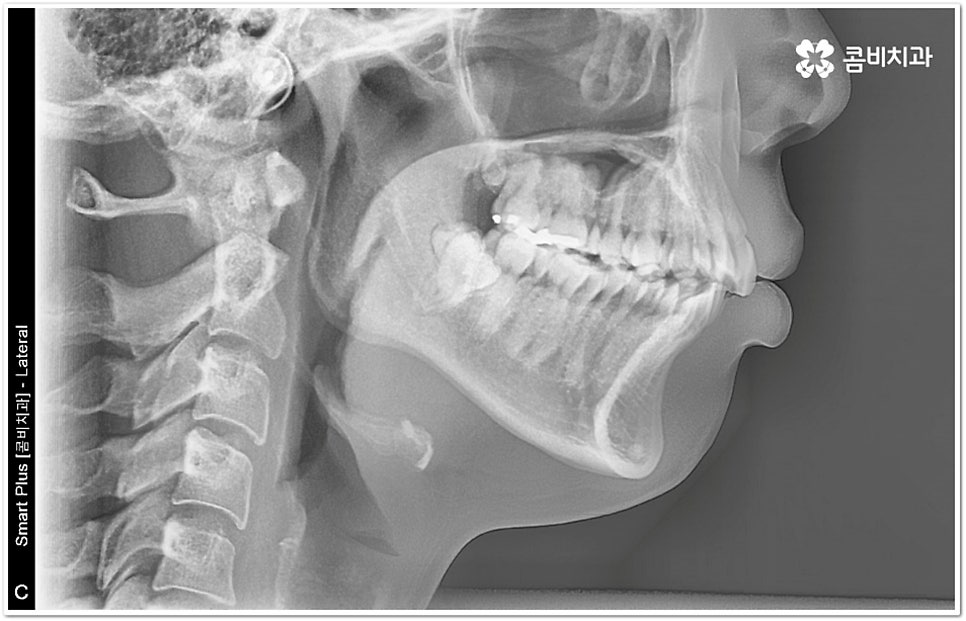

현재는 크게 불편함이 없고 환자분들의 입장에서 볼 때 스스로 교정이 딱히 필요하다고 생각되지 않는다고 해도 정밀 검진을 받아보는 것이 도움이 되는 또 다른 이유는 덧니가 생긴 원인, 구조적인 부분 등을 꼼꼼하게 체크해 봤을 때 혹시라도 추후에 치열이 더 많이 삐뚤어지거나 턱관절에 좋지 않은 영향을 줄 수 있는 상황이라면 미리 대처할 수 있다는 데 있어요. 본을 떠 보고 3D CT 를 이용해 겉으로 보이지 않는 부분까지 함께 살펴보면서 악궁 및 치아의 크기와 각도, 상악과 하악의 발달 정도 등 각자의 상황을 종합적으로 분석해 보면 앞으로의 이동 방향이나 정도 등을 어느 정도 예측해 볼 수 있는데요. 가능하다면 문제가 커진 다음에 바로잡는 것보다 지속적인 관찰을 통해 적절한 시기에 필요한 치료를 하는 것이 시간과 노력을 덜 들이는 방법이 될 거예요.

하지만 모두에게 덧니부분교정 을 적용할 수 있는 것은 아니므로 먼저 3D CT와 같은 정밀 검사 장비를 통해서 턱의 구조적 특성 및 치열과 교합 등 구강 내부 상황에 대해 세세하게 검진을 하고 충분한 상담을 통해 각자에게 적합한 계획을 세운 다음 무리하지 않게 치료를 진행할 필요가 있어요. 만약 부분 교정을 진행할 수 없다고 해도 교정 장치를 이용하여 기간이나 통증 부분의 부담을 덜 수 있으니 너무 실망하실 필요는 없을 거예요.